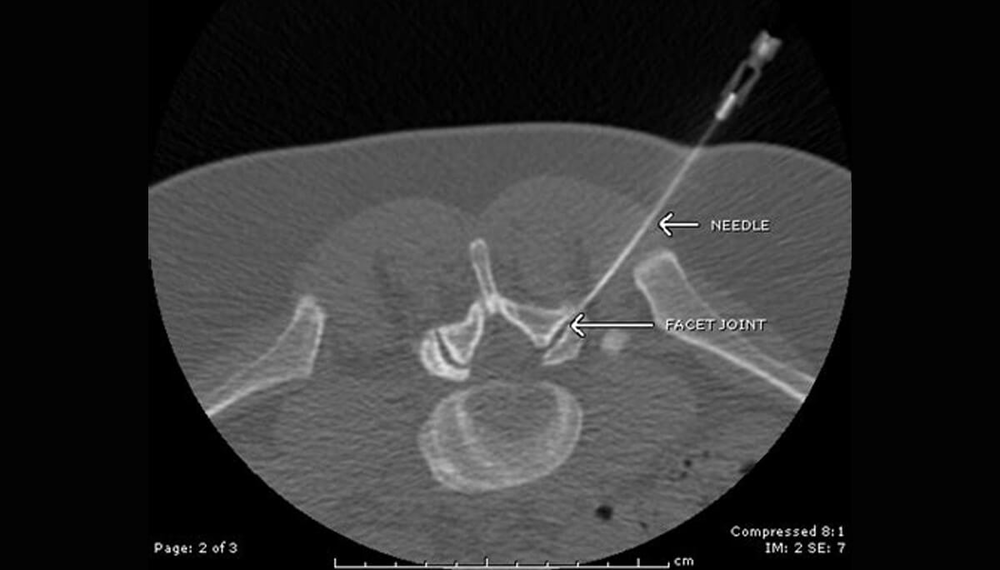

La réalisation de la procédure au scanner permet d’avoir un contrôle précis du bon positionnement de l’aiguille et de permettre une reproductibilité du geste.

On utilise deux types d’abord : une voie foraminale péri radiculaire (à l’étage cervical et lombaire) pour les hernies latérales et une voie épidurale (utilisée uniquement à l’étage lombaire) pour la hernie médiane et le canal lombaire étroit.

Après positionnement de l’aiguille sous contrôle CT, on injecte 0,5cc de produit de contraste non ionique (Omnipaque°) afin de confirmer l’absence de cathétérisme vasculaire. On réalise ensuite l’infiltration avec 5mg/1ml (étage cervical) ou 10mg/2ml (étage lombaire) de Dexaméthasone Sodium Phosphate (corticoïde non particulaire). Pas de précaution particulière en post opératoire. Repos relatif de 24 heures.